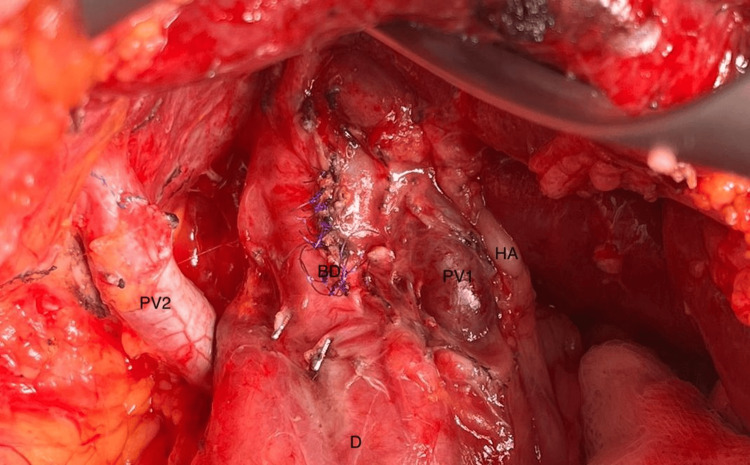

Due to the patient’s previous surgical history, and her preference for an open common bile duct (CBD) exploration was performed, the patient’s anomalous anatomy was identified intraoperatively (Figure 4) behind dense adhesions from her previous operation. Other than meticulous dissection and care during the procedure these findings did not alter the surgical plan or the operation’s course. Postoperatively the patient did very well and she was discharged home on postoperative day 3.